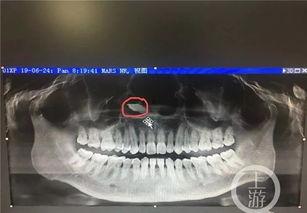

首先,我们要了解什么是牙胚。牙胚是牙齿发育的最初形态,它存在于我们的牙槽骨中。在婴儿时期,我们的牙齿就是从牙胚发育而来的。但是,随着年龄的增长,我们似乎已经告别了长牙的日子。那么,成人怎么长出牙胚呢?

视频中,我们看到了牙胚从牙槽骨中逐渐发育,最终形成完整的牙齿。这个过程虽然复杂,但在视频的讲解下,却显得如此简单易懂。